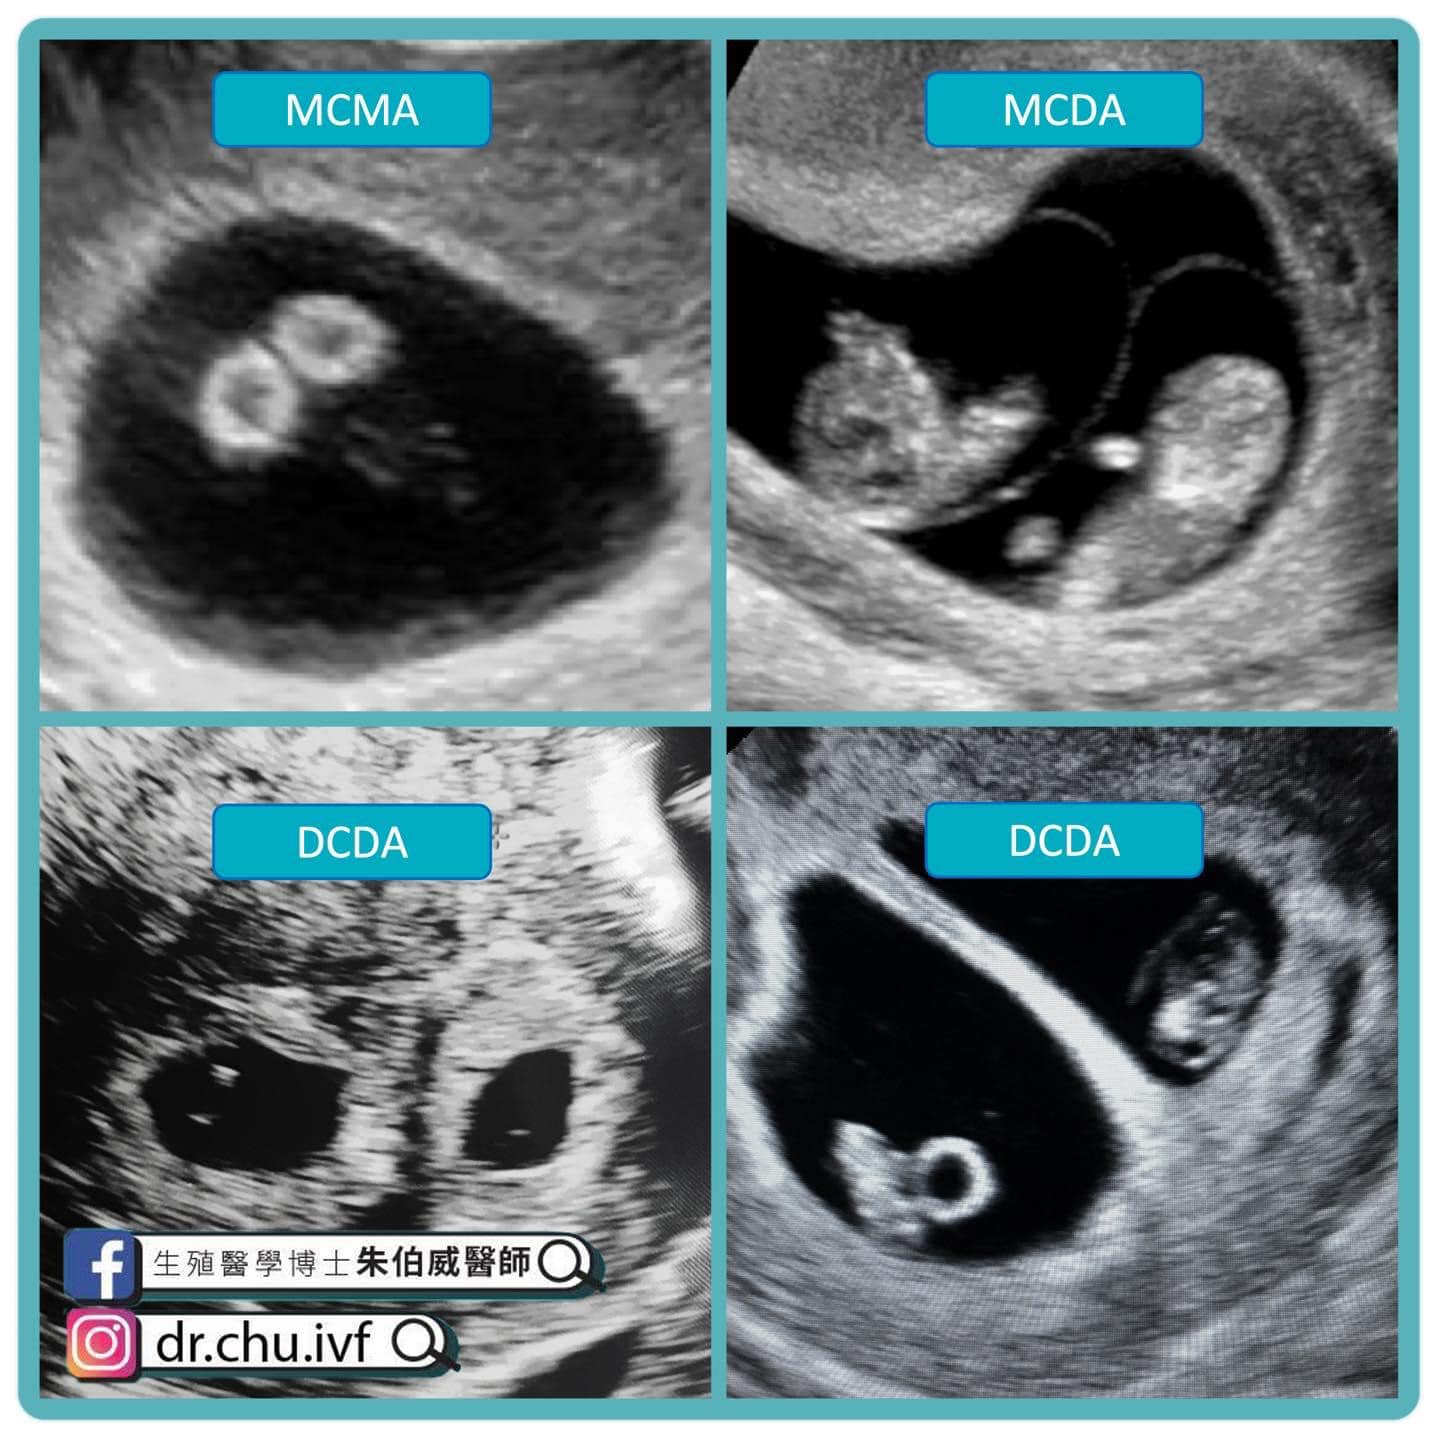

雙胞胎 機率

» 同卵 雙胞胎 機率 (97) 사진

同卵 雙胞胎 機率 (97) 사진